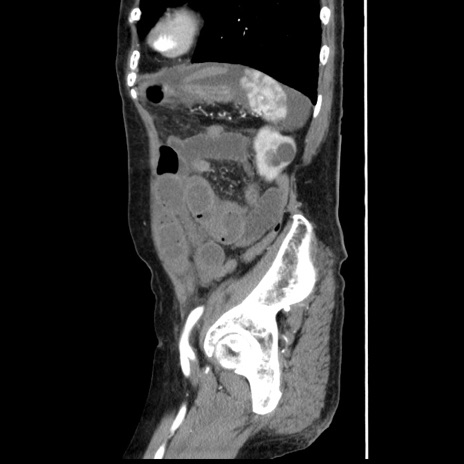

症例1(矢状断像)

【症例】80歳代女性

【主訴】腹痛

【現病歴】8時間前から腹痛あり来院。

【既往歴】糖尿病、脂質異常症、子宮体癌にて子宮全摘術

【身体所見】意識清明・会話良好だが腹痛で苦悶様、全腹部にわたって反跳痛と圧痛あり

【データ】WBC 13600、CRP 0.14、LDH 224、CK 90